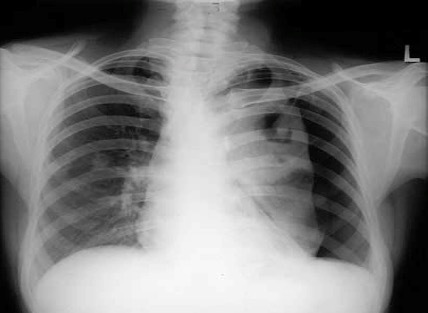

What features are seen on this CXR? What is the likely diagnosis?

Lung markings absent on left

Pneumothorax